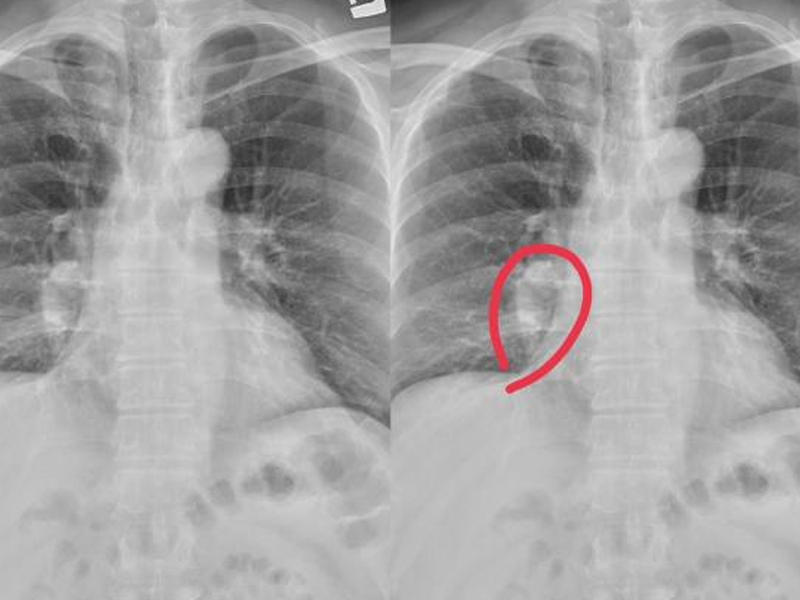

香港 10 癌 1 甲!甲狀腺檢查必須做